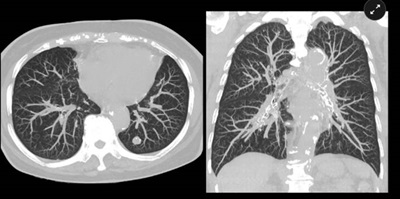

CT (Computed Tomography) Scans

Computed Tomography (CT) scans are a type of medical imaging that provide detailed pictures of the inside of your body. Unlike regular X-rays, CT scans use advanced technology to create cross-sectional images of bones, organs, and tissues. These images help doctors diagnose and monitor a wide range of conditions—from injuries and infections to cancer and heart disease.

In short, a CT scan gives your care team a clear, layered view of what’s happening inside your body, helping them make accurate and timely decisions about your health.